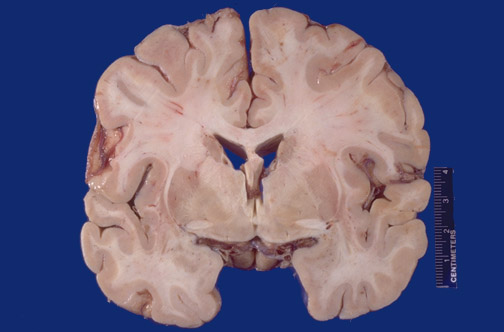

| Identify the following regions of the brain on transverse section in the image above: Caudate Nucleus - Putamen - Globus Pallidus - Anterior Commissure - Nucleus Basalis of Meynert - Corpus Callosum - Sylvian fissure - Insular cortex - Lateral Ventricle - Temporal lobe |